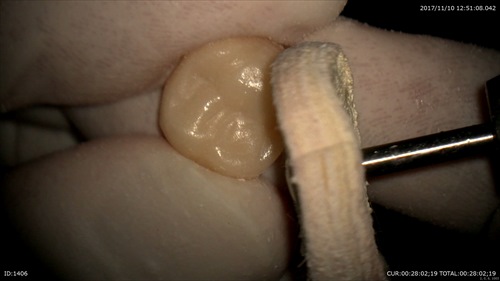

2ケース目:被せ物の型取り前の調整

歯茎を傷つけずに削ります。治療中出血がないのはマイクロのお陰です。

その後仮歯の調整もマイクロスコープで丁寧に